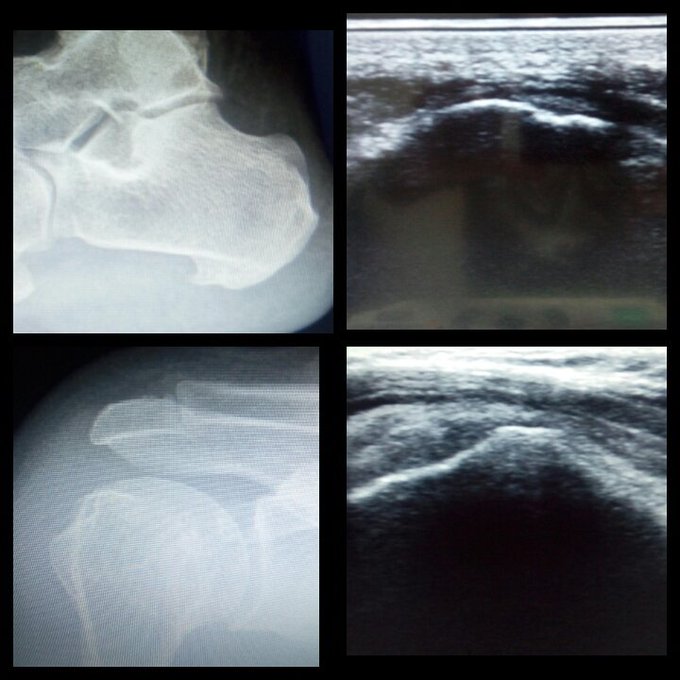

Subacromial impingement and plantar fasciitis due to heel spur diagnosed by ultrasound.

Paciente de 58a quién refiere dolor en hombro izquierdo de 02año de evolución , con dolor y limitacion a los rangos articulares !